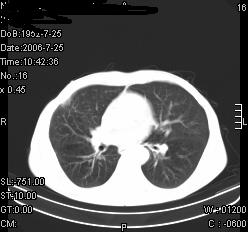

患者,男,54岁,咳嗦,咳痰20天。抗炎治疗2周。现esr76mm/h,目前患者症状明显好转,但发现两次ct片未见明显变化。两次分别做与7.25、7.31。第一次诊断右肺上叶炎症累计胸膜。大家看,从影像上内排除结核吗?

从病灶的形态和分布,我考虑为炎症可能大,是否考虑有机化的可能.当然如能做结核痰检查或结核菌素试验可排除结核的可能.

结核的可能性非常大,右上肺病变应该考虑干酪性肺炎。理由:

3.虽经抗炎治疗肺窗病灶有所吸收、减小,但纵隔窗病灶形态、密度、范围无明显变化。如果是单纯的大叶性肺炎,“抗炎治疗2周,目前患者症状明显好转”病灶应该基本消散了,至少也处于吸收消散期,密度变淡、范围变小。同时本病例所示其内的密度不均匀,见多发大小不一空洞样影也不符合大叶性肺炎吸收消散期表现。

病灶特点:片状 索条 结节混杂影,部分融合,密度不均,广泛累及相应胸膜.

临床治疗;二周未吸收.但症状好转.

多考虑:肺结核.